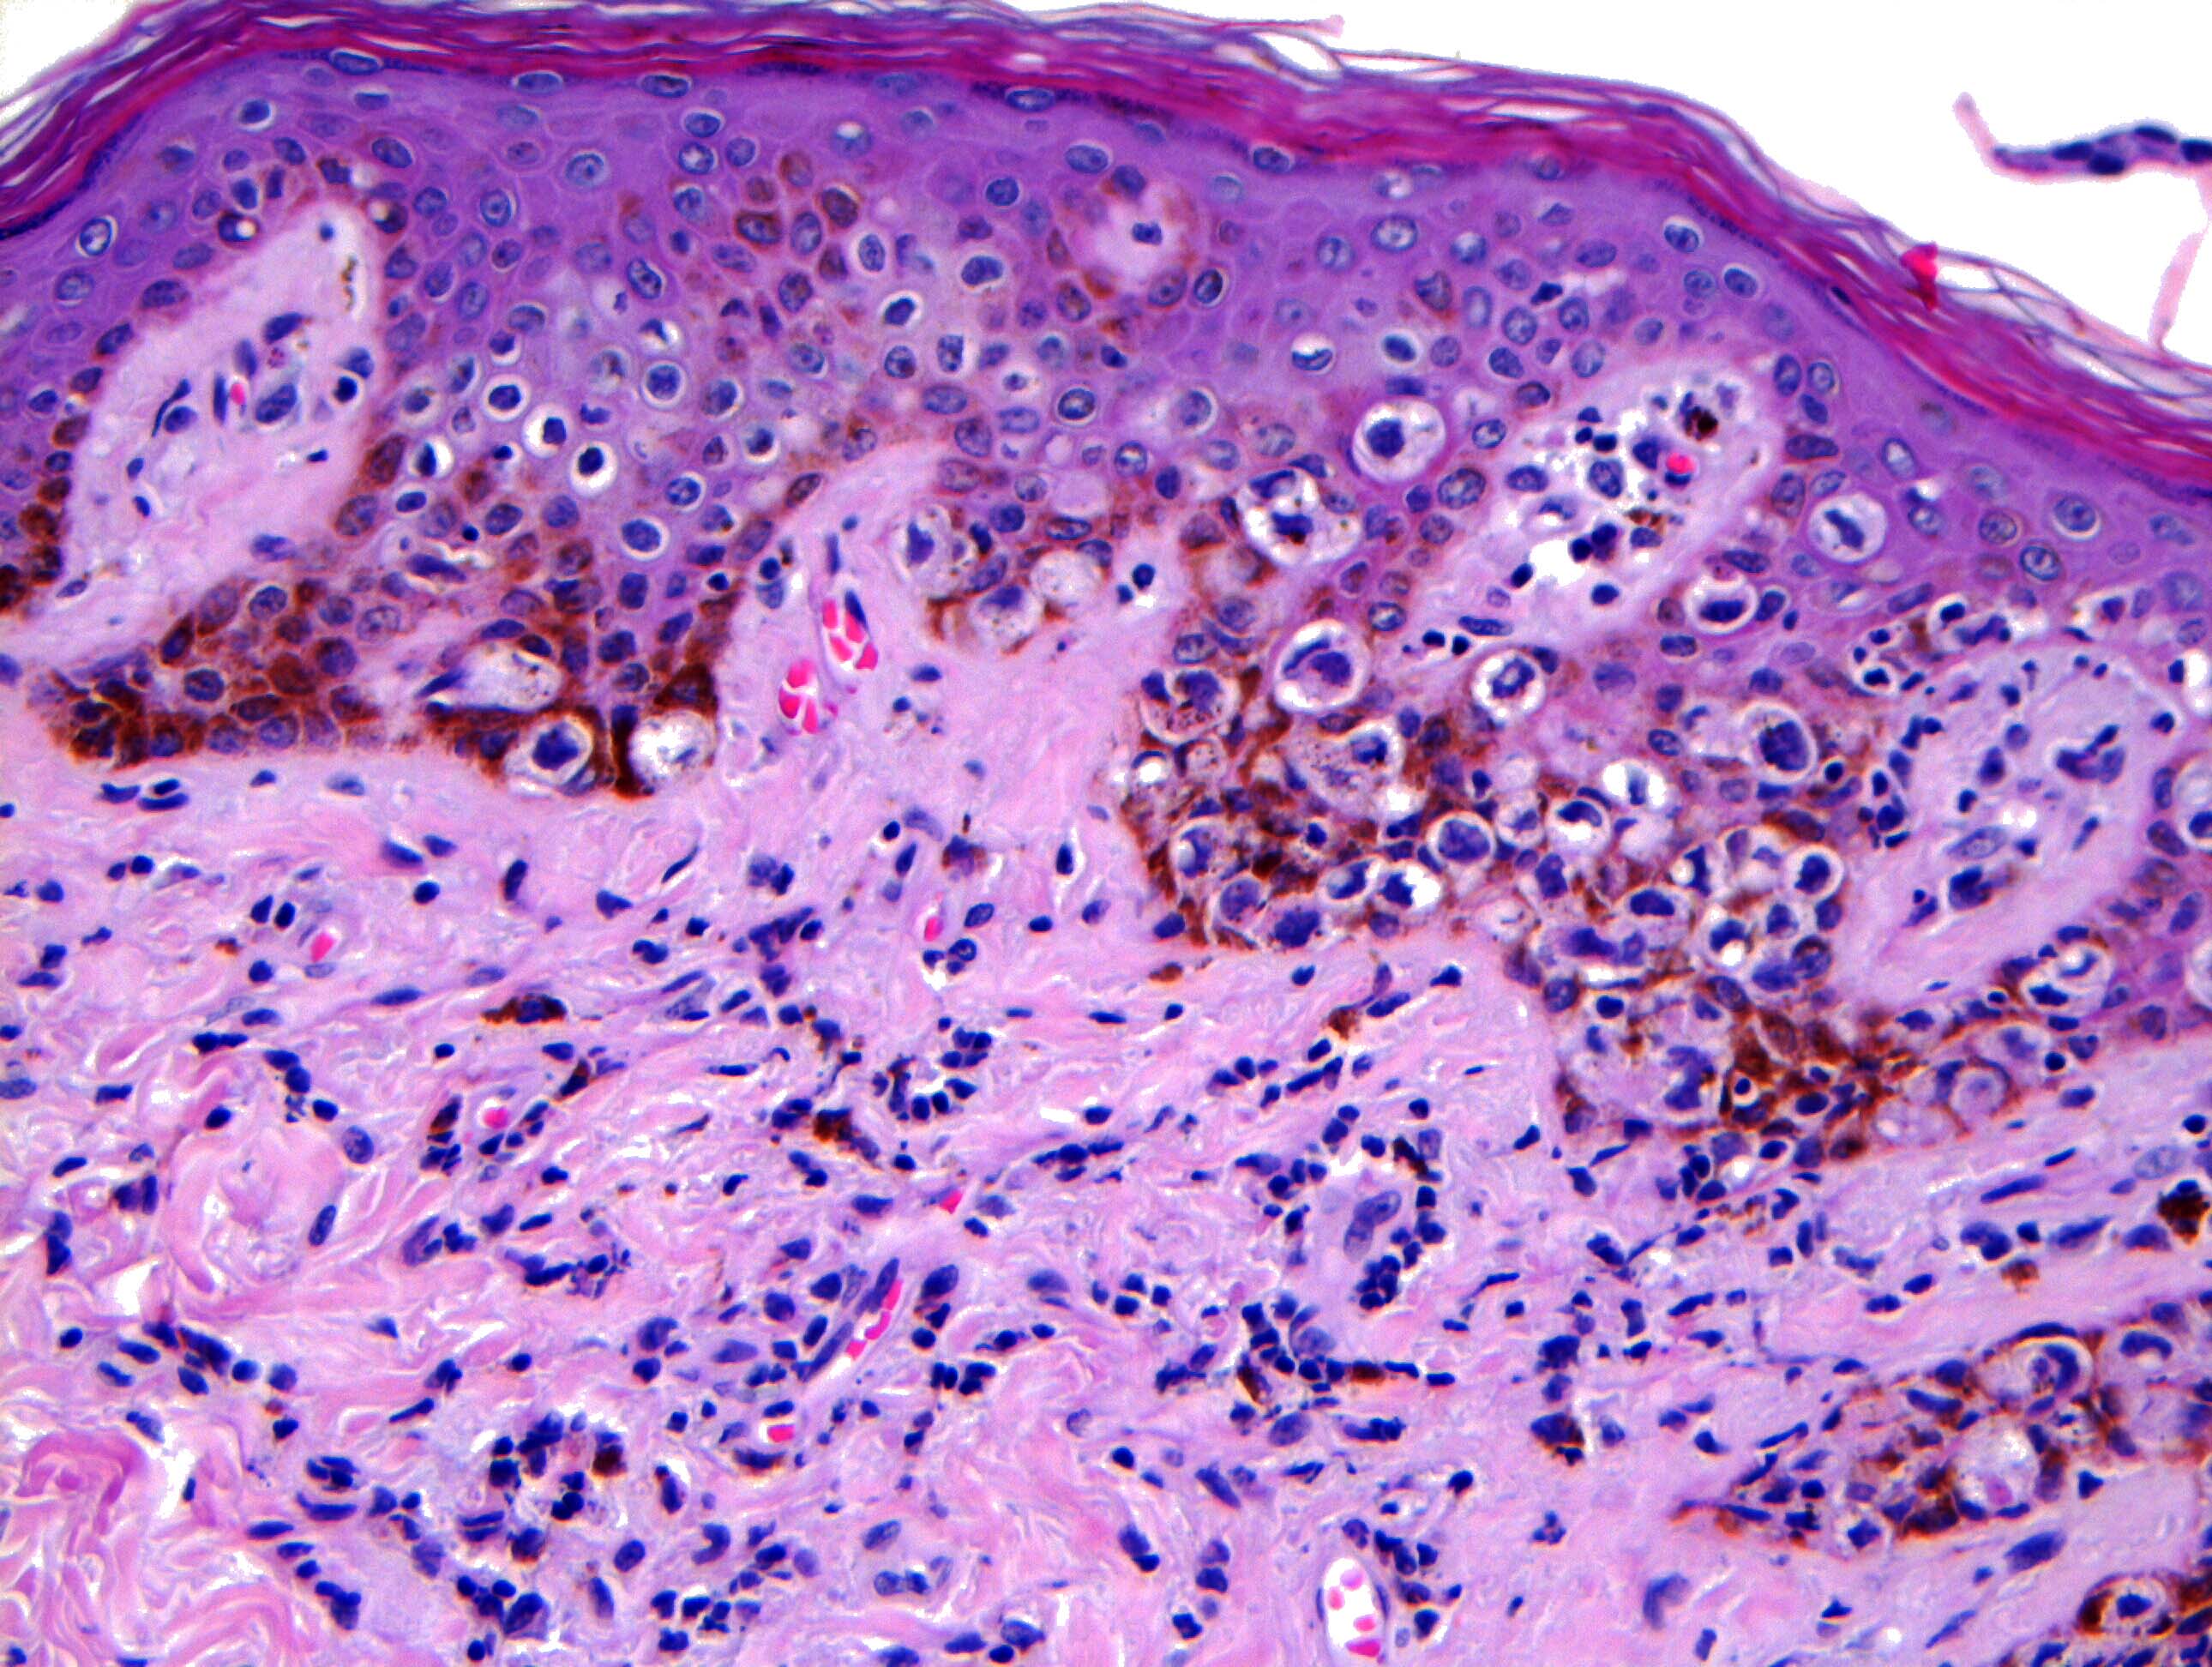

- Single cells or clusters of cells spread throughout the epidermis

- Cells have abundant pale cytoplasm, large irregular nuclei with prominent nucleoli

- Underlying dermis may have chronic inflammation

- Epidermis with hyperkeratosis and possibly ulceration

- Paget cells may phagocytose melanin, mimicking melanocytes

Microscopic (histologic) images

Contributed by Anna Biernacka, M.D., Ph.D. and Mary Ann Gimenez Sanders, M.D, Ph.D.